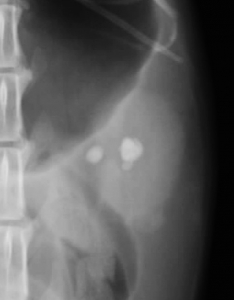

下の写真は両側の腎盂内に比較的大きな腎結石が発見された猫の腹部レントゲン写真です。上写真が縦方向下が横方向のものです。